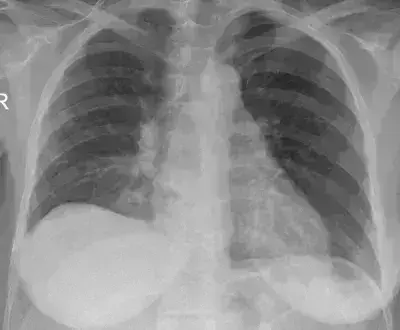

A new study published in the Chest Journal showed that Full MIST2 dosing of intrapleural enzyme therapy (IET)  was Linked to Better Outcomes but infrequently administered and showed substantial variation across hospitals.Patients who received full dosing had a lower risk of treatment escalation or bleeding and experienced a shorter hospital length of stay.

Serious pleural infections with significant morbidity include complicated parapneumonic effusion and empyema. As an addition to drainage, intrapleural enzyme treatment has been developed with the goal of increasing pleural fluid clearance and decreasing surgical referrals. In order to provide practical information on the efficacy, safety, and resource usage of intrapleural enzyme treatment for pleural infection across a range of patient demographics, this study looks at patterns of use and clinical outcomes within an integrated health system. Thus, this study determined how the entire MIST2 regimen dosage of IET varied among 21 hospitals for persons admitted with complex parapneumonic effusion or empyema, as well as the relationships between full MIST2 dosing and outcomes.